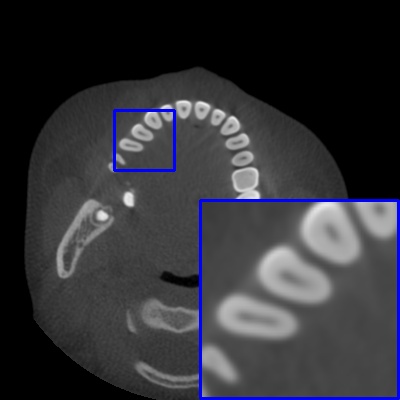

Figure 3: Visual comparison of MAR images by different methods on synthetic MA image. The PSNR (dB)/SSIM results are reported below each image for reference.

Results on synthetic MAR. In Table 1, we provide the quantitative results. One can see that our MARformer-L outperforms the other methods in terms of PSNR and SSIM, but needs only 11.76M parameters and 60.25G FLOPs. Note that the second best method Uformer-B has 50.42M parameters and 205.82G FLOPs. Besides, our MARformer-T achieves similar PSNR and SSIM results with Uformer-T, but needs only 0.40M parameters and 12.82G FLOPs compared to 5.24M and 25.39G for Uformer-T. Our MARformers also achieves faster inference speeds than the Uformers, though with inferior Dice scores, respectively. The qualitative results of visual quality are presented in Fig. 3. We observe that our MARformer-L well recovers the teeth shapes and obtains higher PSNR and SSIM results than the other comparison methods. The light-weight MARformer-L achieves similar results to Uformer-T. All these results validate that our MARformer is more efficient than the comparison methods on dental CBCT MAR.